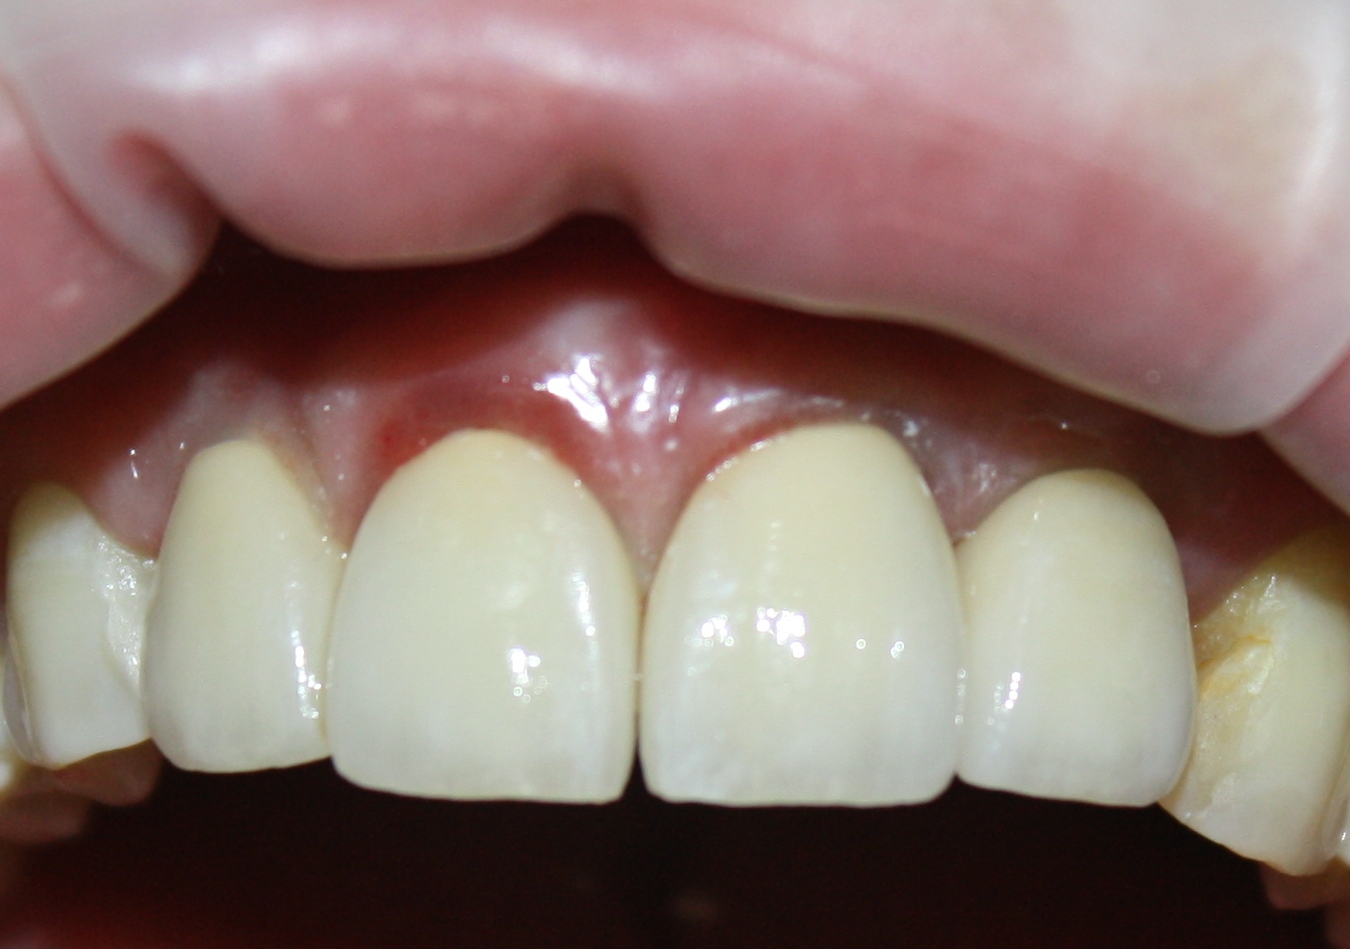

Постоянные протетические конструкции

Через три месяца мы сняли коронки с имплантатов, чтобы оценить качество формирования десневого контура:

С этого момента можно перестать переживать — десневой контур сформировался правильно, мы получили достаточный объём и качество окружающей платформу имплантата десны. Можно приступать к изготовлению постоянной протетики. Подрядчиком стала зуботехническая лаборатория French Creative, одна из топовых лабораторий Москвы.

И вот, в жизни Марии наступил долгожданный день — окончательная фиксация керамических коронок на установленные имплантаты:

При этом, она ни дня не оставалась без зубов, была полностью социализирована и жила обычной жизнью. Спустя 5 месяцев после удаления, поставленную Марией клиническую задачу можно считать решёной. Но это с её точки зрения. С нашей же, всё самое интересное только начинается.